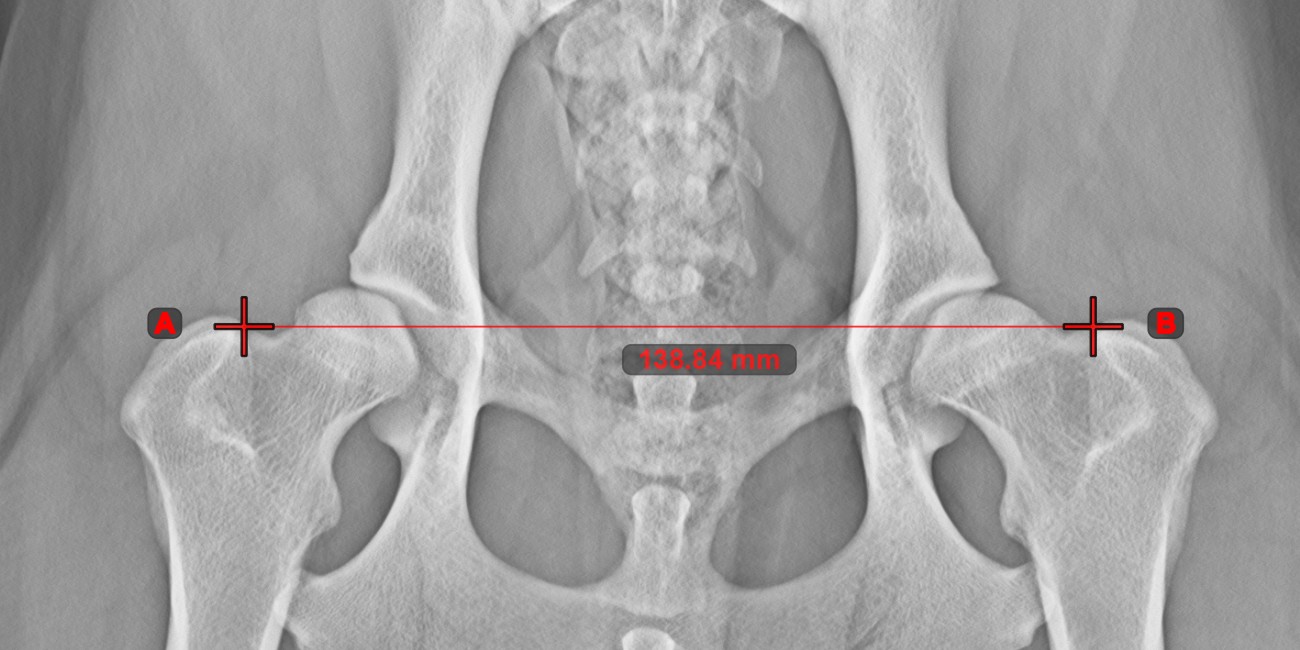

Line Measurement¶

Select the Line Measurement tool and assign it to one of the available mouse buttons. Place the start and end points on the scene or select them from already existing points on the image. The distance between the two points will be automatically

calculated by using the default calibration data, or the recalibrated data by the length calibration measurement.

Modify the start and end point by using the Select/Move Item tool. The distance between the two points will be automatically recalculated.